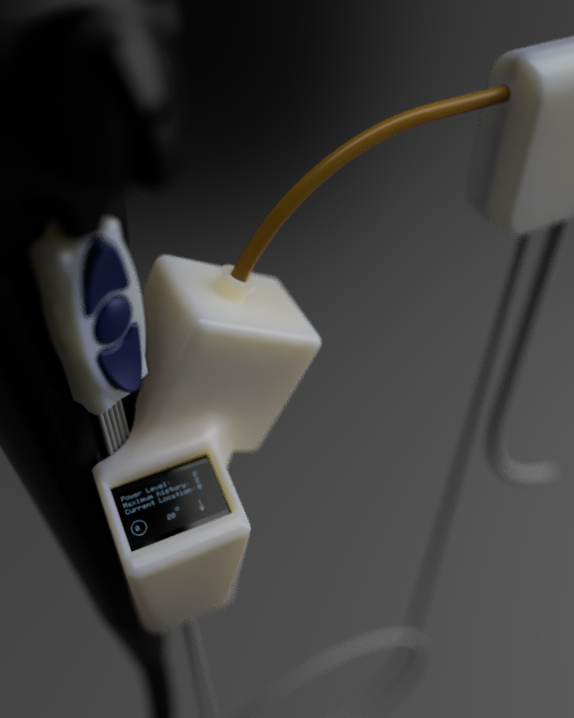

Endoscopic GI Surgical Actuator

Working alongside Dr. Todd Baron and Dr. Lisa Gangarosa at UNC Hospital's Advanced Endoscopy Fellowship, our team identified a clinical need: existing endoscopic tools create post-surgical complications that a redesigned actuator geometry could reduce. I led a team of eight through three years of design, prototyping, and verification — beginning with OR shadowing to understand the procedure environment firsthand.

The design process ran from clinical needs-statement development through ideation sketches — specifying PTFE sleeves, titanium construction, ø2mm working channel geometry, and shape-memory alloy actuation rings — to full parametric CAD and a working proof-of-concept prototype with embedded electronics and an OLED UI displaying power level, machine history, and current position.

All product, manufacturing, testing, and labeling documentation was developed in accordance with ISO 13485, 21 CFR 8xx, and IEC 60601-1, managed throughout in Greenlight Guru QMS. Prototype fabricated across UNC's fabrication facilities using available in-house methods.